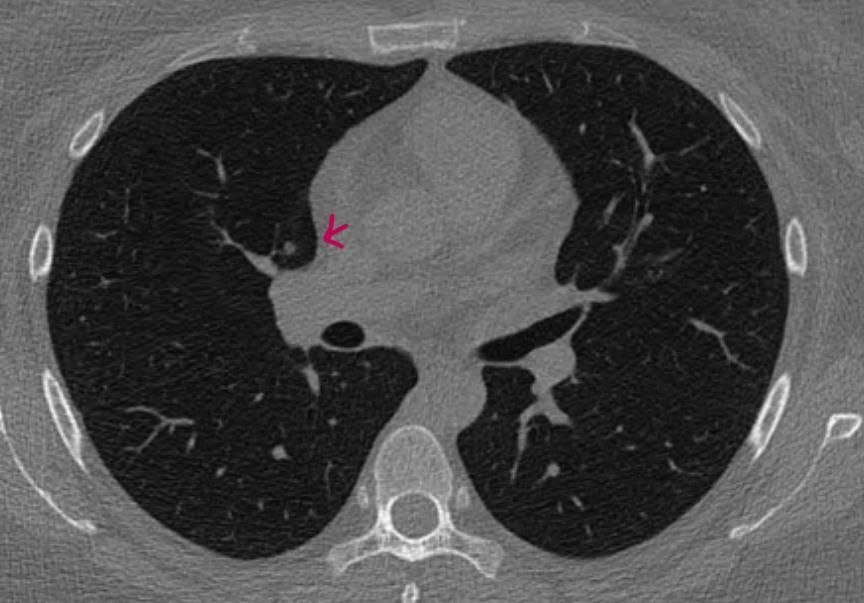

간유리 결절 같나요 고형인가요. 그 외 질문 부탁드려요

*좀더 하얀색인 사진 2장은 24년 조영제 폐CT 이고, 나머지 3장은 25년 저선량 CT사진입니다.

♧ 고형 같나요 간유리 같나요?

Ai 는 우상엽 solid라는데 오늘 2차병원에서 중간위치고 간유리에 가깝다라고 들어서요

solid nodule인지 ground glass nodule인지는 clear cut하게 나누어지는 것이 아닙니다. 결절이 색이 또렷하면 solid nodule인 것이고 흐지부지하면 ground glass nodule인 것입니다. 이건 육안 소견을 두고 말하는 것입니다. 따라서 일부 nodule에 있어서는 판독하는 의사에 따라 소견이 다를 수 있습니다.